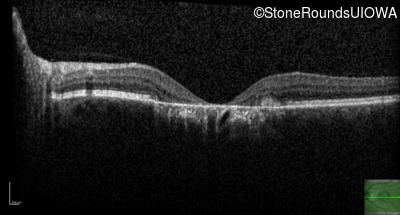

Pattern Dystrophy (IIC)

Age at visit: 51 years

This 51 year old woman first noticed some metamorphopsia in her left eye in her early 30's.

Pattern Dystrophy PRPH2 IVS2+3 A>T   AD